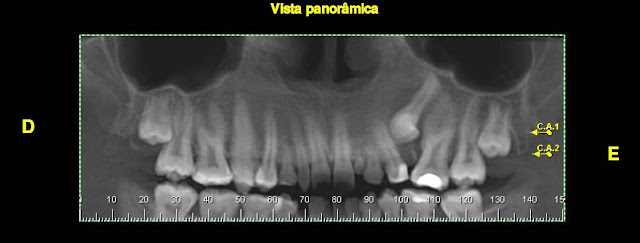

Vejam pelas imagens tomográficas que o canino 23 está retido por vestibular, retenção esta causada pelo elemento 25, que está retido por palatina, em posição horizontal, e com a coroa atipicamente voltada para distal, próxima à coroa do 23.

| Reconstrução panorâmica |

Além disso, haviam outras complicações como restos radiculares de dentes decíduos no leito cirúrgico e presença de sentes conoides e decíduos erupcionados.

Optamos pela remoção do 25 por acesso palatino, e manutenção do 23 com colagem de aparatologia ortodôntica (laçada) para o seu posterior tracionamento. Caso muito interessante.